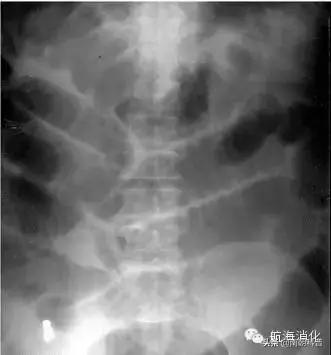

浠讳綍涓嶆槑鍘熷洜鐨勮吂鐥涳紝搴斿父瑙勮吂閮ㄥ钩鐗囨鏌ャ€傝吂鐥涘悗4-6灏忔椂鍑虹幇姘旀恫骞冲拰鏄庢樉鑲犵绉皵鎵╁紶鏃讹紝鍗冲彲璇婃柇鑲犳闃伙紝鍚屾椂锛岃繕鍙尯鍒槸灏忚偁姊楅樆杩樻槸澶ц偁姊楅樆銆佹満姊版闃昏繕鏄夯鐥规闃伙紝鍔ㄦ€佽瀵熷彲鍙嶆槧鑲犳闃荤殑鐥呮儏鍙樺寲锛屽洜姝わ紝鑲犳闃诲彂鐢熷悗鏈€濂芥瘡1-3澶╂媿涓€寮犺吂閮ㄥ钩鐗囷紝鐩村埌姘旀恫骞冲拰鑲犵Н姘旀秷澶便€?/p>